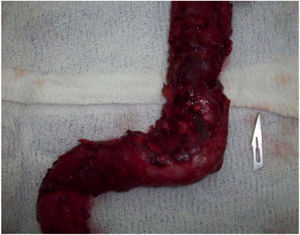

The primary surgery was palliative colostomy in 3 patients, one of whom had left hemicolectomy (Fig. 1). Four patients underwent right hemicolectomy. The remaining patient was diagnosed endoscopically with adenomatous polyposis and underwent total colectomy in the second surgery.

One patient had 9 hyperplastic polyps in the first surgery and several adenomatous polyps were observed in the duodenum and colon in the following endoscopies, but none of her family members presented with familial adenomatous polyposis (FAP) (Figs. 2 and 3).